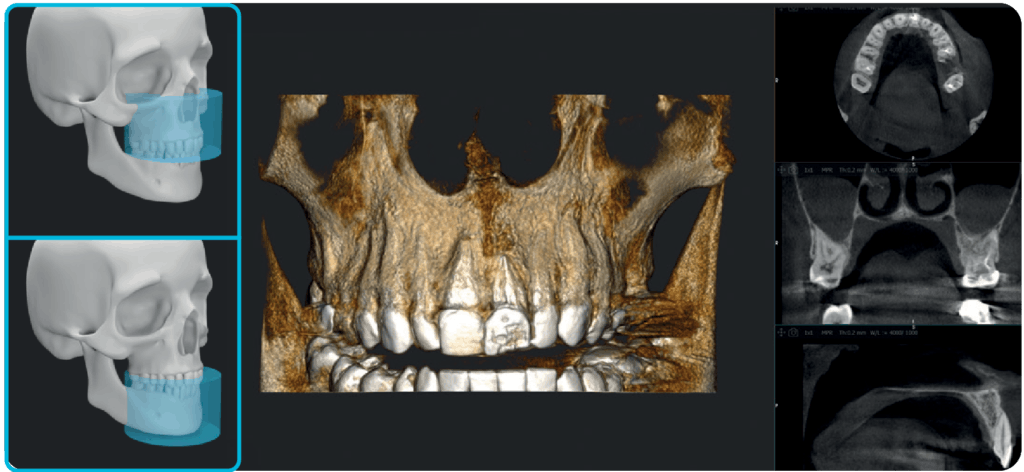

X-MIND® optima to połączenie nowoczesnych technologii w lekkiej, kompaktowej konstrukcji z innowacyjnym, łatwym w obsłudze oprogramowaniem RealGuide™ 5.4. Dzięki wykorzystaniu sztucznej inteligencji rozwiązanie to wspiera stomatologów na każdym etapie pracy – od precyzyjnej diagnozy, przez efektywne planowanie leczenia, aż po optymalizację wydajności pracy gabinetów stomatologicznych i usprawnienie komunikacji z pacjentami.

X-MIND® optima łączy zaawansowaną technologię sprzętową z oprogramowaniem nowej generacji RealGUIDE 5.4, wprowadzając zalety sztucznej inteligencji do każdego etapu opieki nad pacjentem.

Oprogramowanie RealGuide 5.4 wykorzystuje technologię AI, aby maksymalnie ułatwić i usprawnić pracę lekarzom na każdym etapie leczenia implantoprotetycznego, zapewniając lepszą komunikację z pacjentami, budując zaufanie i poprawiając wskaźniki akceptacji leczenia.

Upraszczając złożone zadania i automatyzując kluczowe procesy, oprogramowanie usprawnia cały proces, umożliwiając szybsze i dokładniejsze planowanie leczenia.

Wykrywanie łuku zębowego

Śledzenie przebiegu nerwu

Segmentacja zębów

Segmentacja kości

Pozycjonowanie implantu